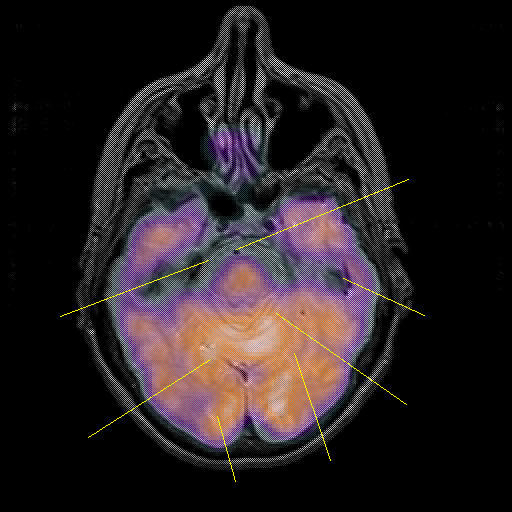

overlay : Slice 17

Slice 17

Pointers

Labeled